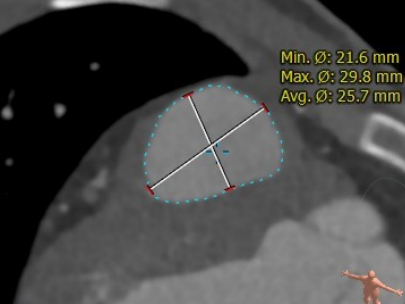

患者男性,19岁,法洛氏四联症根治术后12年。超声提示肺动脉瓣重度反流、三尖瓣中度反流。术前行详细影像学重建与评估,主肺动脉腰部截面为不规则形,径宽22-30mm,形态测算植入介入瓣后直径26mm。术中肺动脉造影测量与术前评估一致。手术经胸入路,在TEE引导下,经右室流出道穿刺植入26号Salus介入肺动脉瓣,术后TEE提示肺动脉介入瓣植入位置理想、固定良好,无瓣周漏及中央反流。

CT重建肺动脉

主肺动脉腰部截面